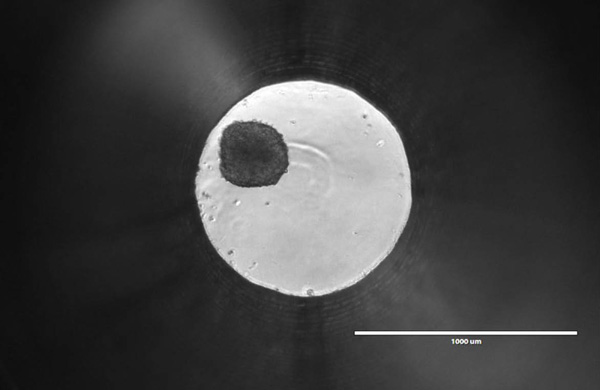

In 2D culture, cells are typically plated in a flat monolayer. One-sided attachment induces a polarity that is unnatural for many cells. It also means that each cell is getting equal access to nutrients and oxygen, resulting in uniform growth and proliferation. Each cell is likely at the same metabolic state, which is rare in the body. Tumors, in contrast, show high levels of heterogeneity, with some cells actively proliferating, others quiescent, and some necrotic. This issue is less prevalent in 3D spheroids, where nutrient gradients emerge gradually as the diameter increases. As the spheroid grows, the cells in the core begin to experience reduced oxygen exposure. This results in a hypoxia gradient, which can lead inner layers to quiescence and even necrosis.